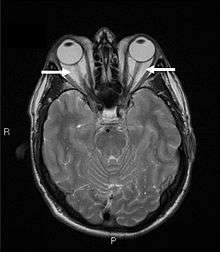

Orbital imaging is an interesting tool for the diagnosis of Graves' ophthalmopathy and is useful in monitoring patients for progression of the disease. It is, however, not warranted when the diagnosis can be established clinically. Ultrasonography may detect early Graves' orbitopathy in patients without clinical orbital findings. It is less reliable than the CT scan and magnetic resonance imaging (MRI), however, to assess the extraocular muscle involvement at the orbital apex, which may lead to blindness. Thus, CT scan or MRI is necessary when optic nerve involvement is suspected. On neuroimaging, the most characteristic findings are thick extraocular muscles with tendon sparing, usually bilateral, and proptosis.